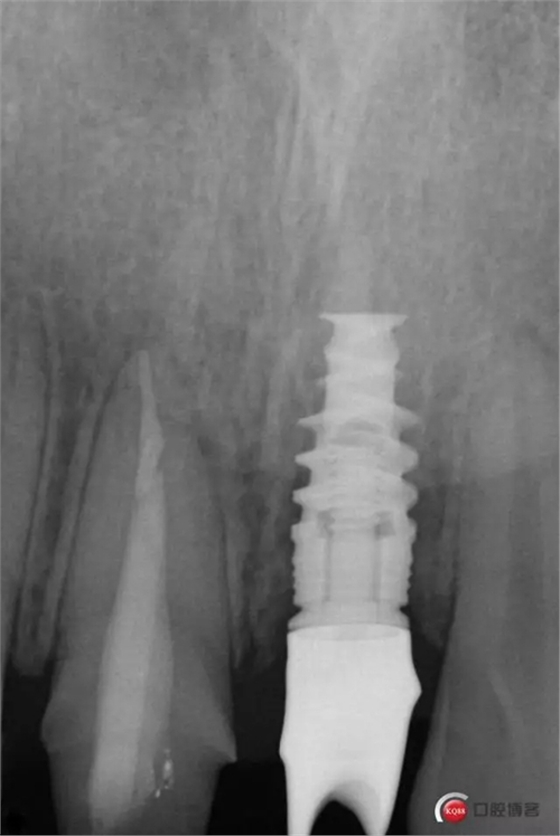

種植后修復(fù),我們要把握每一個(gè)細(xì)節(jié),比色,轉(zhuǎn)移桿的就位,我們必須把臨床做好,技工師傅才會(huì)給我們做出好的修復(fù)體,減少一些不必要的失誤,首先術(shù)前的檢查是必要一步 ,再是器械的準(zhǔn)備使我們臨床操作有條不紊,術(shù)前拍照,o-bite取咬合記錄,消毒修復(fù)術(shù)區(qū),旋出愈合基臺(tái),生理鹽水沖洗袖口,拍照袖口,安放合適轉(zhuǎn)移桿,拍X線見(jiàn)轉(zhuǎn)移桿就為良好,硅橡膠取模,術(shù)后旋回愈合基臺(tái),拍照比色。

藻酸鹽對(duì)頜取模,超硬石膏灌注。發(fā)加工廠,與技工溝通注意事項(xiàng),等修復(fù)體做好后,檢查模型。是否就位,是否密合,預(yù)約患者復(fù)診戴牙,消毒修復(fù)區(qū),旋出愈合基臺(tái),定位器指導(dǎo)安放修復(fù)基臺(tái),試戴冠,調(diào)磨鄰接及 咬合至合適,拋光,患者滿意,加力扳手加力至30N,拍X片見(jiàn)就位良好,特芙蓉及暫封膏封中央螺絲孔,聚羧酸鋅粘固劑粘固,或是樹(shù)脂水門汀粘固,清理多余粘結(jié)劑,光固化樹(shù)脂封螺絲孔,拋光。術(shù)后注意隨訪。